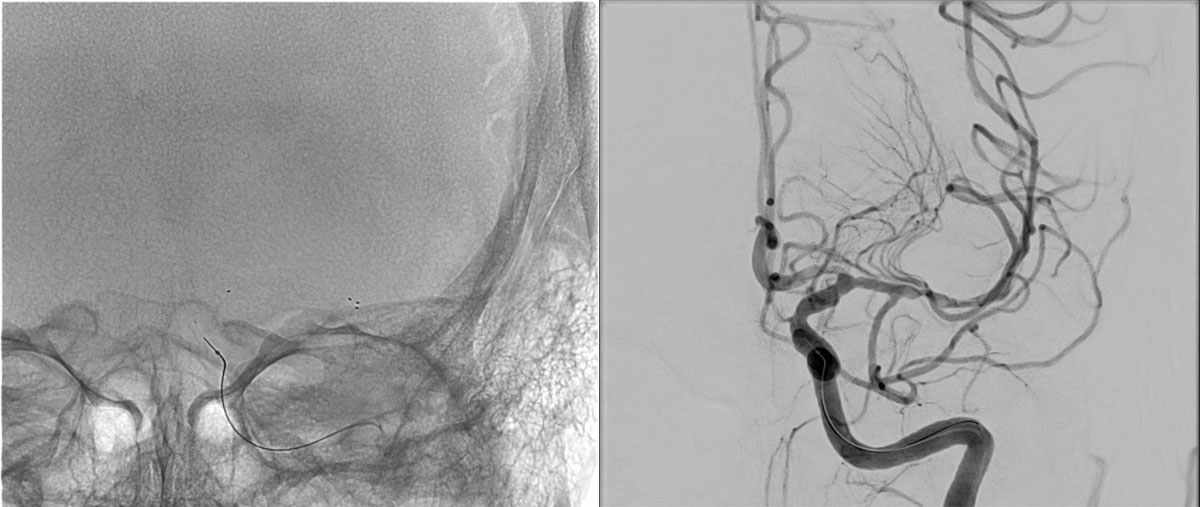

ICA-M1 intracranial dissection EVT

This clinical case presents a 28-year-old female patient presenting with a wake-up stroke, managed with endovascular treatment.

DSA

L - VERT

L - ICA